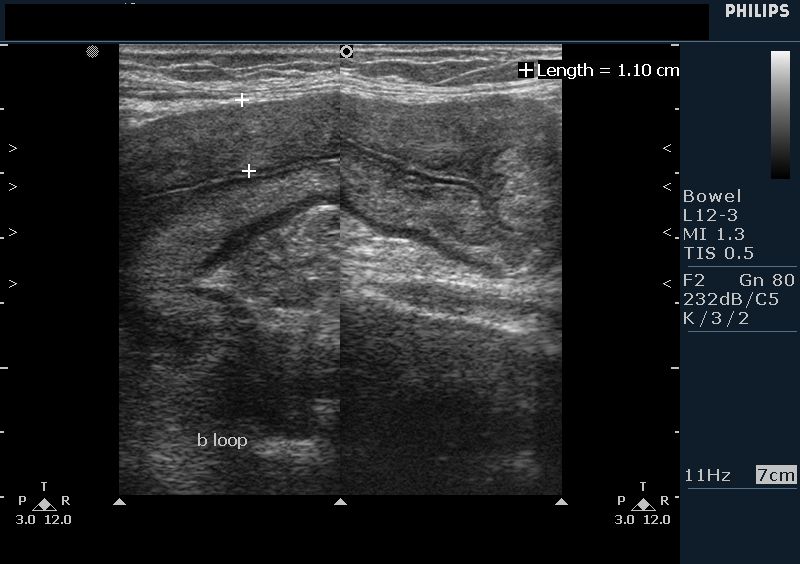

While segmental or diffuse bowel thickenings are usually caused by benign condition such as ischaemia, inflammatory and infectious conditions.

The colonic wall thickens in many conditions. There are several serious underlying conditions, most of which need to be discussed with a doctor and treated. Colon cancer is sometimes called colorectal cancer, which is a term that combines colon cancer and rectal cancer, which begins in the rectum.

The colon is associated with inflammatory pathology such as ulcerative colitis in which there is inflammation and prolonged exposure to the disease can. Diverticulitis causes a thin colon wall. Colon cancer is sometimes called colorectal cancer, which is a term that combines colon cancer and rectal cancer, which begins in the rectum. If you suspect neoplastic thickening, what should you look for (outside of the colon).